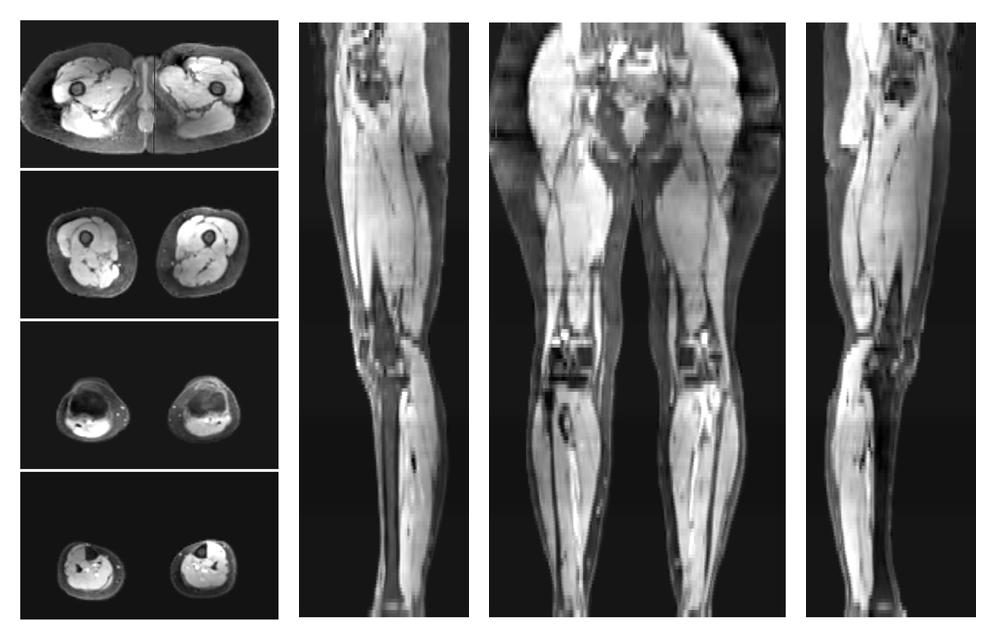

• Water only signal

The water part of the acquired multi-echo spin echo data.